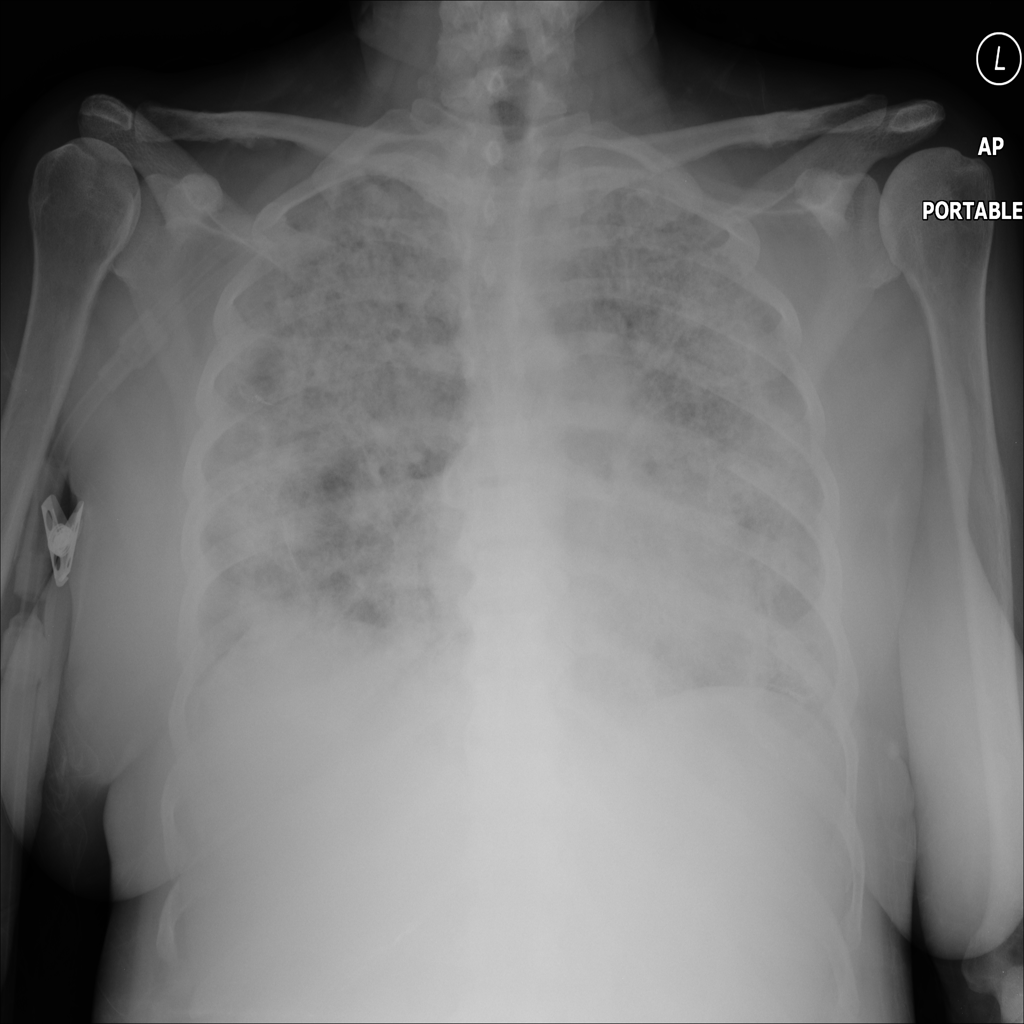

PAT-4DA0 · IMG-004Consolidation

PAT-4DA0 · IMG-004

AP